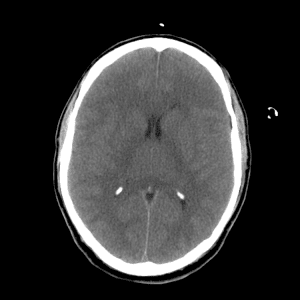

PCA infarct